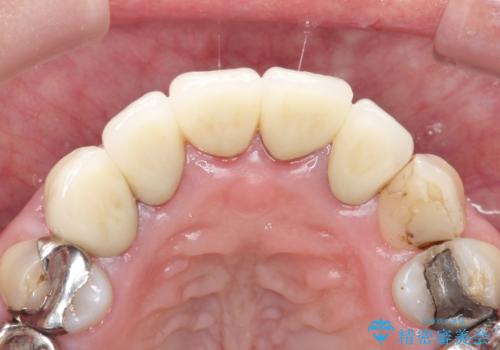

上の前歯の根元が黒い 根の治療を含めたセラミック再治療

- 上の前歯の根元が黒くなっているので、再治療をしたいとのことで来院された患者様です。

レントゲンを撮影すると、適合不良のかぶせ物が装着されており、根の治療も不十分であることが確認されました。

適合不良のかぶせ物をすべて除去して、根の中の治療から再治療を行うこととなりました。

適合不良のかぶせ物が装着されていた歯は、内部がやはり虫歯になっていました。

かぶせ物だけではなく見えないところも、精密な治療をすることが重要となります。